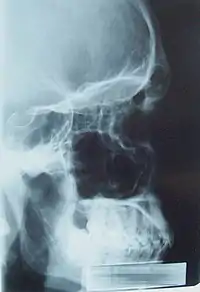

Sinusurile paranazale sunt un grup de patru spații-pereche umplute cu aer care înconjoară cavitatea nazală.[1] Sinusurile maxilare sunt situate sub ochi; sinusurile frontale sunt deasupra ochilor; sinusurile etmoidale sunt între ochi iar sinusurile sfenoidale sunt în spatele ochilor. Sinusurile sunt numite dupa oasele faciale în care acestea sunt situate.

- Sinusurile maxilare, cele mai mari dintre sinusurile paranazale, sunt sub ochi, in oasele maxilare (deschise în partea din spate a hiatusul semilunar al nasului).

- Sinusurilor frontale, superioare ochilor, în osul frontal, care formează partea dura a fruntii.

- Sinusurilor etmoidale, care sunt formate din mai multe celule de aer în osul etmoidal între nas și ochi.

- Sinusurile sfenoidale, în osul sfenoid.